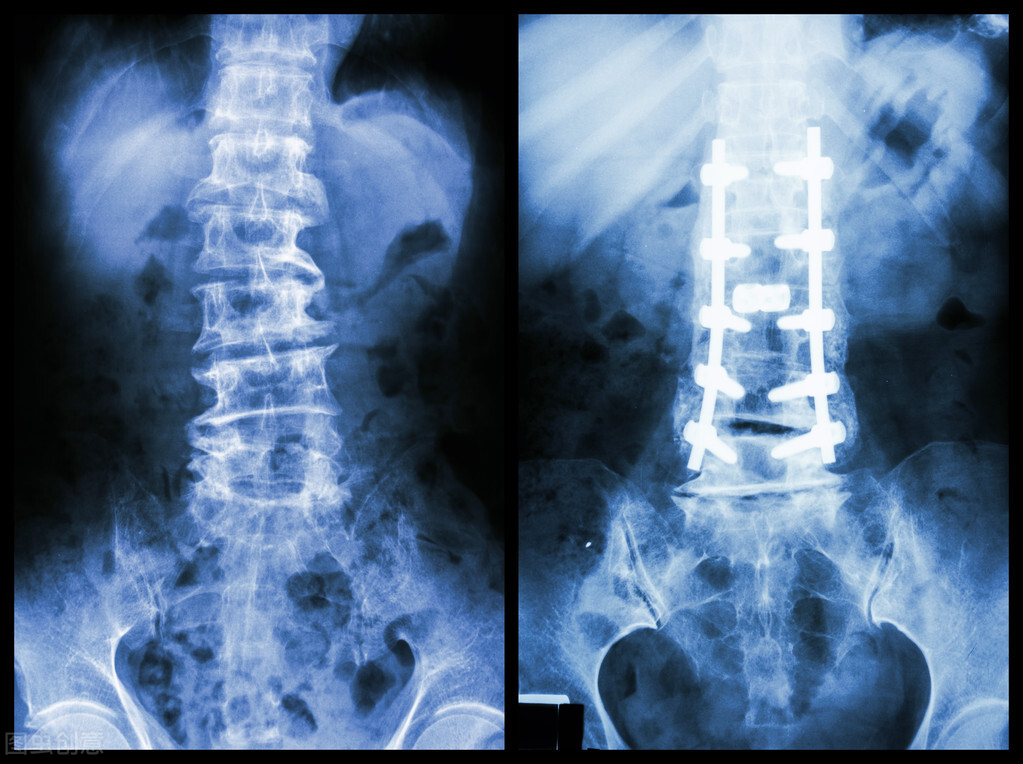

当然除了骨折之外,一些其他骨科疾病可能也需要用到金属内固定物,比如:腰椎和颈椎的相关疾病,也可能需要用到金属固定物。

但是,钛合金内固定物,在做核磁共振检查的时候,虽然患者的健康安全没问题,但是在做检查时会对核磁信号产生影响,在成像的时候会看不清楚,比如腰椎内固定物做出来的核磁共振图像, 会非常模糊,看不清楚。